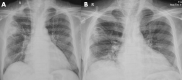

Severe coronavirus disease (COVID-19) is currently managed with systemic glucocorticoids. Opportunistic fungal infections are of concern in such patients. While COVID-19 associated pulmonary aspergillosis is increasingly recognized, mucormycosis is rare. We describe a case of probable pulmonary mucormycosis in a 55-year-old man with diabetes, end-stage kidney disease, and COVID-19. The index case was diagnosed with pulmonary mucormycosis 21 days following admission for severe COVID-19. He received 5 g of liposomal amphotericin B and was discharged after 54 days from the hospital. We also performed a systematic review of the literature and identified seven additional cases of COVID-19 associated mucormycosis (CAM). Of the eight cases included in our review, diabetes mellitus was the most common risk factor. Three subjects had no risk factor other than glucocorticoids for COVID-19. Mucormycosis usually developed 10-14 days after hospitalization. All except the index case died. In two subjects, CAM was diagnosed postmortem. Mucormycosis is an uncommon but serious infection that complicates the course of severe COVID-19. Subjects with diabetes mellitus and multiple risk factors may be at a higher risk for developing mucormycosis. Concurrent glucocorticoid therapy probably heightens the risk of mucormycosis. A high index of suspicion and aggressive management is required to improve outcomes.